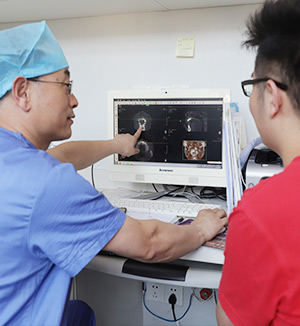

通过数字化系统,模拟种牙的位置、角度、深度。

3D可视导板协助,融入微创技术,精准植入。

姜医生表示:“在数字化3D导板的辅助下,种植手术过程缩短了至少1/3的时间,术后创口小、恢复快,大大提升了整个种植过程的效率。同时可对无牙颌患者口腔的美观和功能进行更优化的设计和更合理的修复,为无牙颌种植提供了很大的便利。”